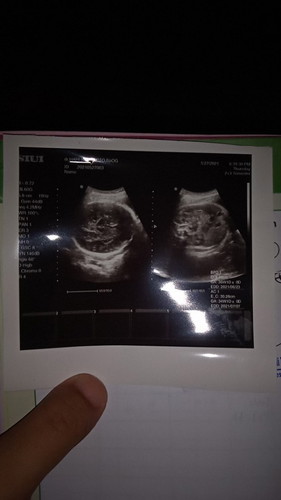

Bun mau tanya kmren saya usg,itu di gambar umur kehamilannya berbeda kan itu ada 2 tulisannya yg diatas 36wk yg bawah 34wk Sedangkan menurut hpl skrg baru 35wk Yg bener brpa ya bun,,soalnya dari kmren saya sma sodara saya masih ributin itu😁 Maaf soalnya kehamilan prtama #seriusnanya #ingintahu #jangandibully #firstbaby Yg ngasih tau makasih ya 🥰 smoga yg lagi nunggu dede launching dikasih kemudahan